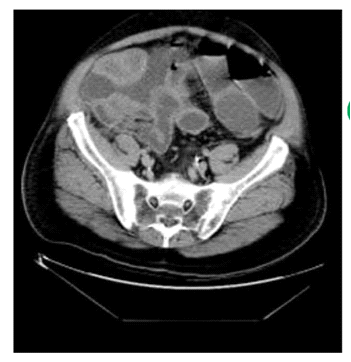

לעתים רחוקות, כדי לקבוע את גובה החסימה ואת מידתה בחולים הלוקים בחסימה דינמית, או כדי להבדיל בין שתי צורות החסימה, יש לצלם את החולה לאחר בליעת חומר ניגוד נספג מסוג גסטרוגרפין. בחסימה דינמית ניתן למצוא התקדמות של חומר הניגוד עד לחסימה (תצלום 6.4), ואילו בחסימה אדינמית ניתן למצוא אמנם מעבר לכל אורך המעי, אך מעבר איטי ביותר. לחולים שבהם יש חשד לחסימת הכרכשת, אין לתת בריום דרך הפה אלא לבצע חוקן בריום תחילה. ב- CT בטן עם חומר ניגוד ניתן לראות לולאות מורחבות שלאחריהן לולאות התמט, בצקת של הלולאות ונוזל ביניהם (תצלום 7.4).